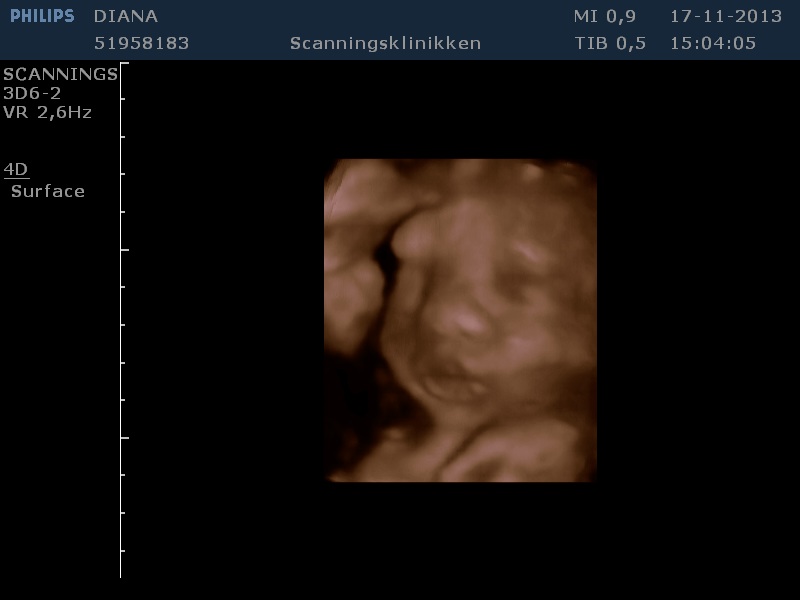

Noah

Vi venter i spænding på du kommer ud til os ❤️